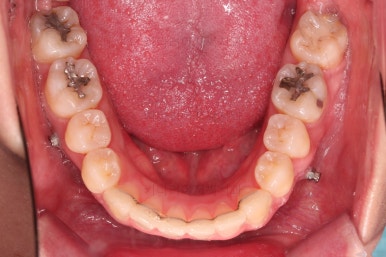

부산비대칭교정 마무리 때의 입안의 모습입니다.

가지런한 느낌은 좋지만 정중선 당연히 약간 안맞고요.

폭도 100%는 안맞아서 어금니쪽이 약간 애매한 교합이기도 했습니다.

하지만 이정도의 비대칭 상황에서 이정도의 교합은 교정만으로 할 수 있는 베스트가 아닌가 생각됩니다.